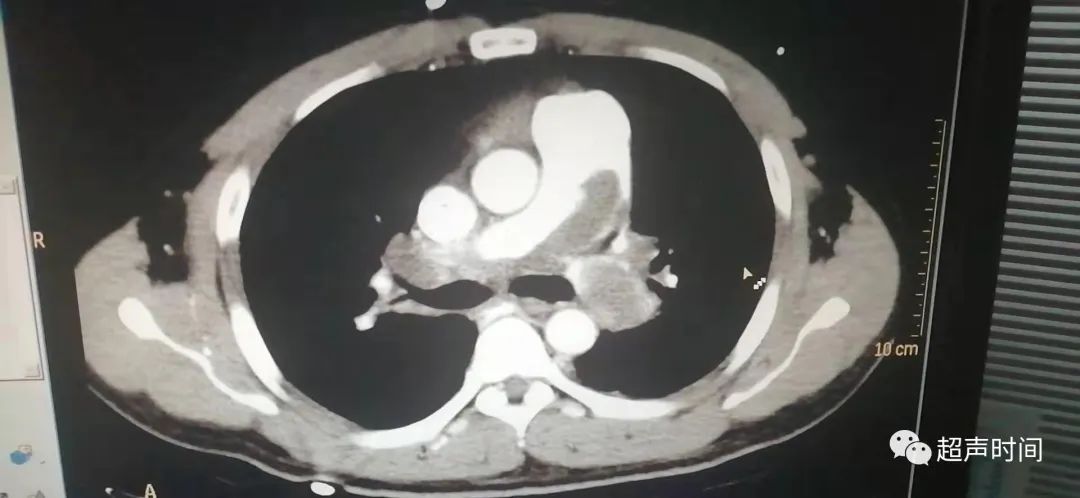

随后患者行肺动脉增强 CT 检查,证实双侧肺动脉广泛血栓形成。

肺动脉造影是诊断 PTE 的金标准,但由于为有创检查,通常选择肺动脉增强 CT 检查。